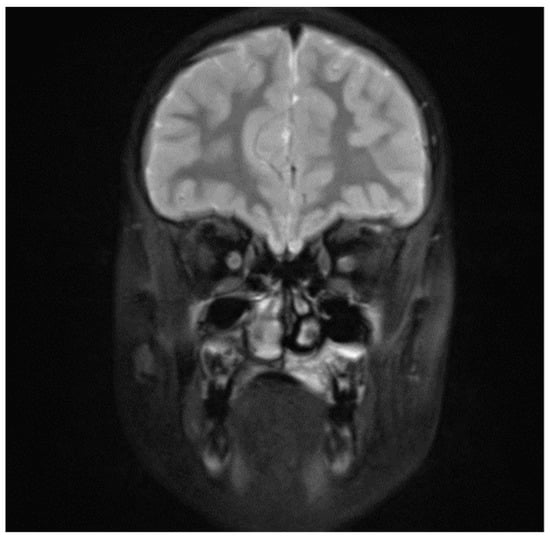

The 8-year-old patient was referred to the Children’s Dental Clinic because of trauma of front upper central incisors. Hypermobility of the left upper incisor with swelling and bloody petechiae of the upper lip were noticed. Because the periapical X-ray was inconclusive, a CBCT examination (NewTome 3G, 110 kV, 2 mA, 18 s) of the maxilla was performed to evaluate the possible presence of a fracture of either the root or the alveolar bone. CBCT ruled out the presence of a fracture in the front upper region but revealed the presence of a soft-tissue mass covering the area of the hard palate and extending into a maxillary sinus and a nasal cavity, which had dimensions of 25 × 25 × 20 mm (Figure 4). Clinical re-examination showed a dome-shaped enlargement of the palate extending from the midline to the palatal aspect of tooth 26 (FDI). A non-shifting mass of medium consistency was covered with pale, normal-looking soft tissue. The adjacent teeth showed normal vitality and mobility, and no palpable lymphadenopathy was observed. The patient underwent an open biopsy of the palatal mass. Histopathological examination revealed a high-grade B-cell lymphoma (Figure 5). The patient then underwent an extent-of-disease evaluation. MRI examination in the TSE, T1 and T2, and fluid-attenuated inversion recovery (FLAIR DWI) sequences was performed. An increase in signal intensity with thickening of the palatal mucosa on the left side was observed with a blurred pattern of the alveolar bone in the region of teeth 26 and 27 and post-contrast enhancement (Figure 6). A positron emission tomography (PET-CT) examination did not reveal the presence of other outbreaks of the disease in the regions of the head and neck, abdominal cavity, pelvis, or skeleton. On the basis of the results of the extended examination, the patient was classified into stage III and the low/intermediate treatment group according to the EICNHL-COG Inter-B-NHL-2010 protocol, and a 7-day cytoreductive prephase COP was initiated. Subsequently, the patient completed two cycles of COPADM and two CYM cycles without Rituximab. Because of an unsatisfactory response to the chemotherapy, supplementary treatment was introduced with two additional cycles of R-CYVE (Rituximab, Cytarabine, and Etoposide). Finally, the patient responded well to the therapy, and remission was achieved. Currently, seven years after the initial diagnosis, he undergoes regular check-ups, including dental examinations. The intraoral lesion resolved completely because of chemotherapy, and no surgical treatment was performed.

Figure 6. Patient, 8 y.o.: Coronal section MRI T2 fast spin fat-saturation image, increase in signal intensity with thickening of the palatal mucosa on the left side.